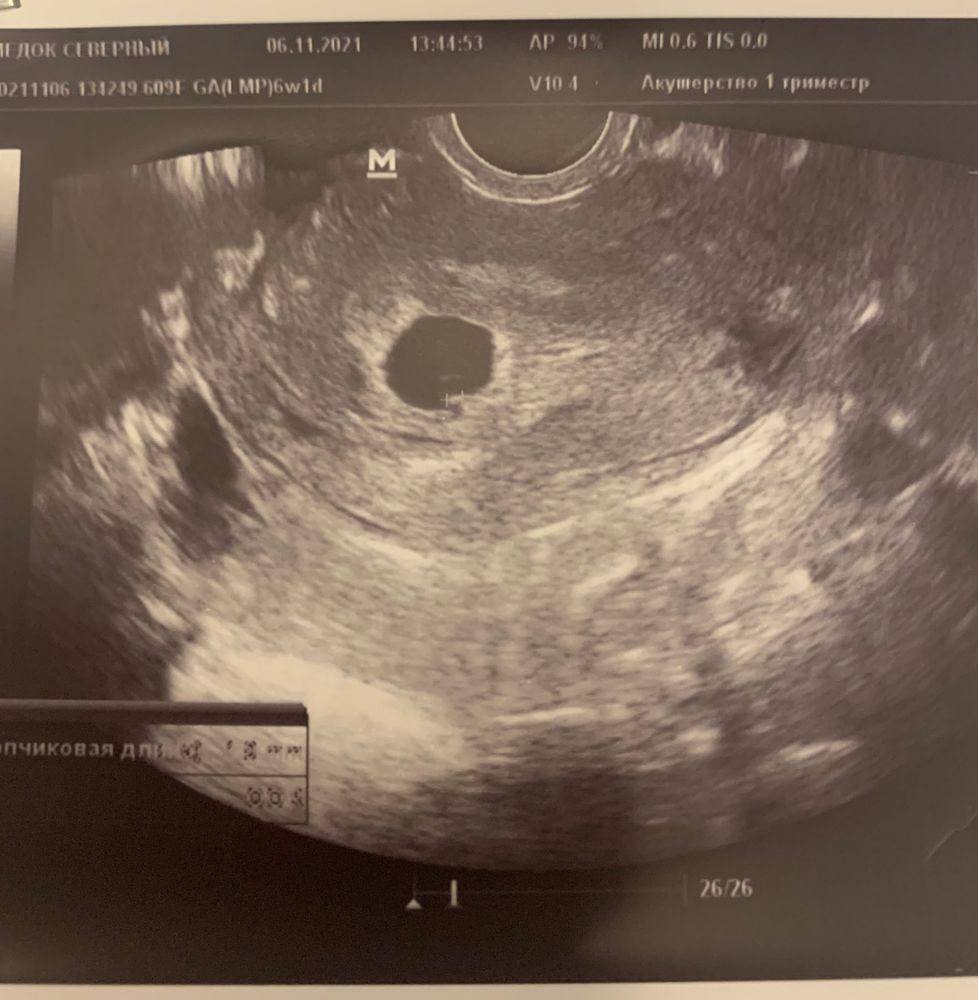

Мое маленькое чудо❤️🙏узи

УЗИ, КТГ, доплерСВД 13,6мм, КТР 1.9мм, ЖМ 3.5 мм, хорион кольцевидный 5.5 мм, ЧСС-96 уд.мин✨

врач сказал все хорошо, но назначил узи через неделю ещё разок. По мес. Срок 6.1, по узи 5+2, норма?